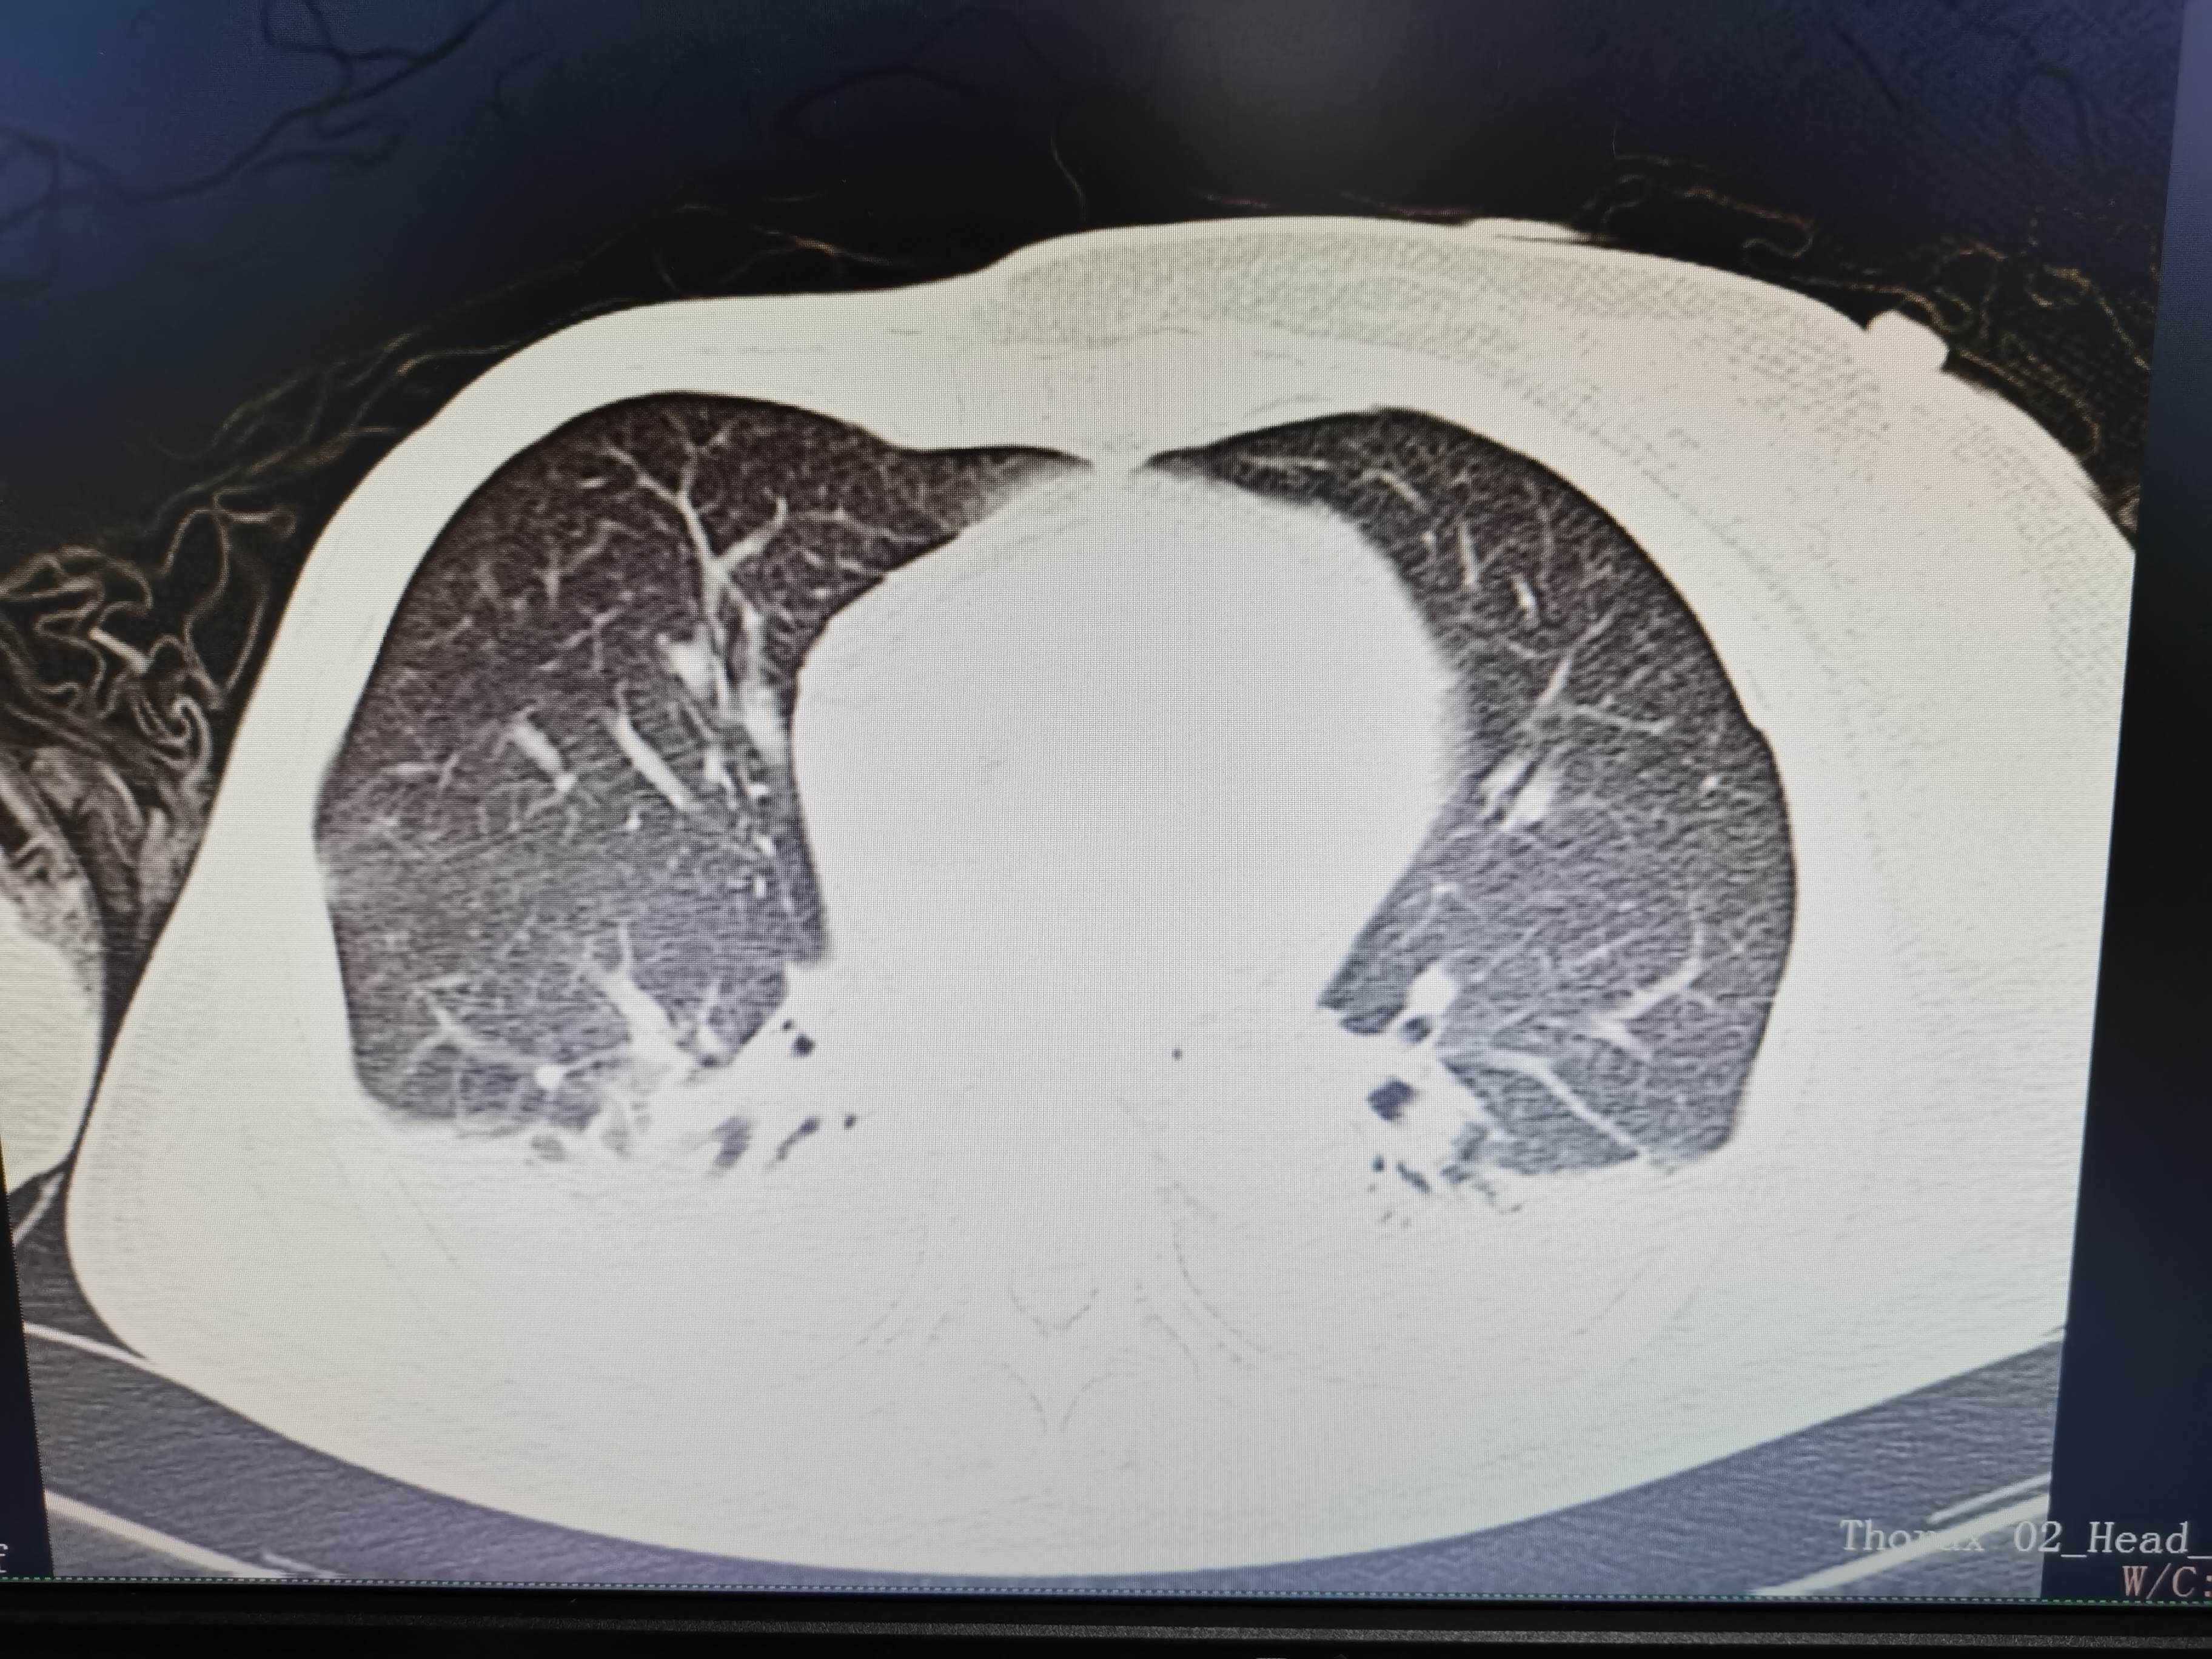

西门开心 推荐63岁女性,因车祸致短暂神志不清、多处疼痛4h入院。简单病史:伤后送至医院急诊就诊。完善头胸腹CT等检查,完善新冠核酸、血常规等化验。血常规提示血红蛋白62g/L。头颅CT提示未见明显外伤性改变。胸腹部CT视频见下:

5.肺挫伤

6.双侧多发肋骨骨折

12.双侧胸腔少量积液

早上复查血常规:血红蛋白100g/L,白细胞11.1×109/L,血小板29×109/L。凝血功能:APTT37.9s,纤维蛋白原3.01g/L,凝血酶时间18.6s,D二聚体21530ug/L。生化:白蛋白36.2g/L,胆红素指标正常,谷丙56U/L,总胆红素38mmol/L,直接胆红素12.1mmol/L,谷草57U/L,肌酐91.1ummol/L,尿素13.97mmol/L,超敏C反应蛋白142.1mg/L。降钙素原17.70ng/ml。脑钠肽前体2164pg/ml。复查胸部CT:

那么问题来了,出现呼吸衰竭气管插管的病因是?请大家讨论分析!